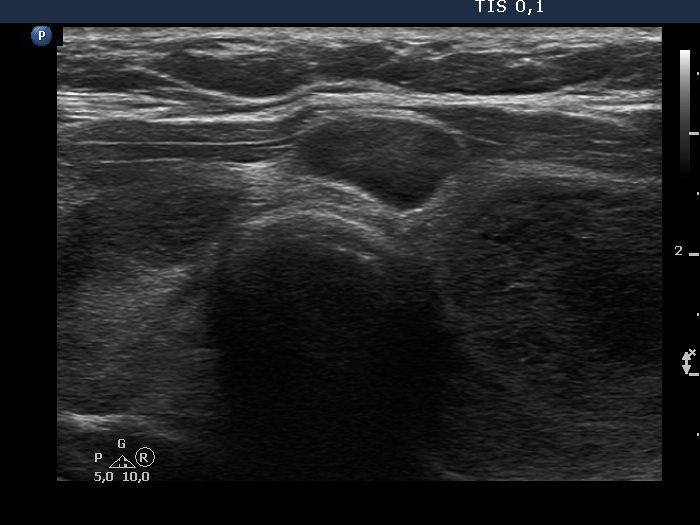

First examination (first, third and fifth rows of images):

Clinical presentation: A 48-year-old woman requested a thyroid evaluation. She was diagnosed with a low grade, stage III/A non Hodgkin lymphoma two years ago. On the first and subsequent PET CT scan, no progression was detected, and on all occasions multiple foci were described within the thyroid. The patient hasn't got any therapy yet.

Palpation: Both thyroid lobes were a bit firm, but no discrete lesions could be palpated. Numerous firm lymph nodes were palpable at both sides of the neck.

Laboratory tests: TSH 1.56 mIU/L, anti-TPO 0 U/mL, ahTg below 20 U/mL.

Ultrasonography. The thyroid was echonormal and contained multiple inhomogeneous, partly blurred hypoechogenic and moderately hypoechogenic discrete lesions. Multiple lymph nodes were found on both sides of the neck.

Cytology was performed from 3 different thyroid lesions and resulted in a pattern corresponding to non Hodgkin lymphoma.